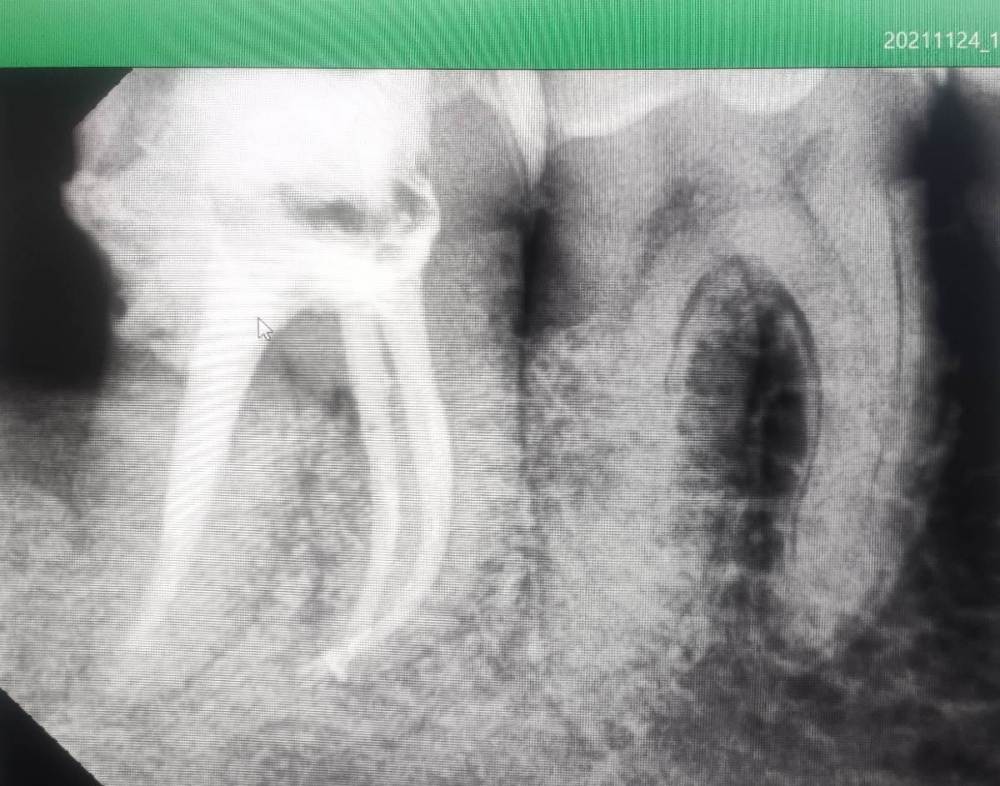

Александр9 Опубликовано 24 ноября, 2021 Автор Поделиться Опубликовано 24 ноября, 2021 спасибо за ответы! Впервые наблюдал за лечением своего зуба на экране. С микроскопом оказалось действительно лучше, т.к. зуб достаточно глубоко был поражен и приходилось тщательно его "вычищать" изнутри. Правда в стенке все же образовалась дырка и пришлось ее заделывать "заплаткой". На снимке видно темные области под временной пломбой. Это не помешает проходить с ней 4 месяца до установки коронки? 1 Ссылка на комментарий

St. Опубликовано 26 ноября, 2021 Поделиться Опубликовано 26 ноября, 2021 По снимку все красиво! Под такой временной пломбой может быть неконтрастный материал или "ваточка". Тем не менее долго ходить с временной пломбой не стоит и чем быстрее Вы попадете на восстановление и коронку тем лучше (меньше риск что отколите остатки стенок и повторного попадения микробов). Кстати, если вдруг временная выпадет, обязательно показаться доктору и вернуть ее на место. без временной ходить категорически нельзя. 1 1 Ссылка на комментарий